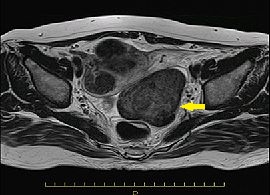

MRI画像(T2強調画像)

下腹部痛の増悪を認め、近医受診。腹部超音波検査にて骨盤内腫瘤、腹水貯留を指摘され、当院へ紹介受診。CT検査にて、子宮多発筋腫を認め、精査の結果、漿膜下子宮筋腫茎捻転と診断。手術を施行した。